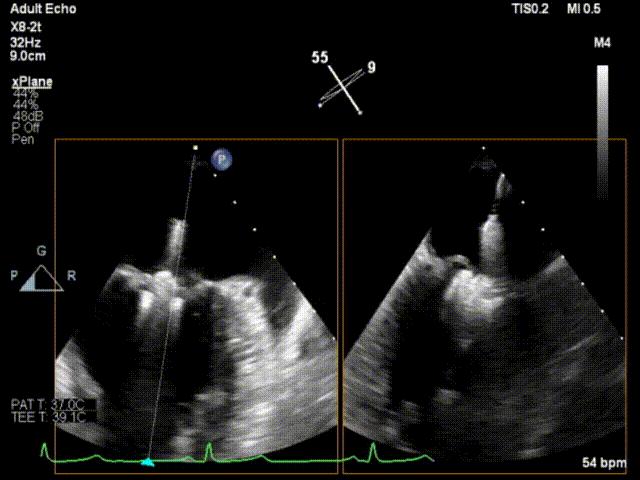

释放夹子

术后即刻超声心动图

术后即刻超声3D